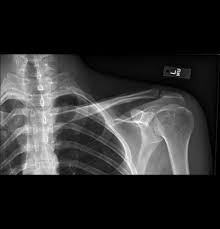

Clavicle X Ray Positioning : Shoulder Clavicle Scapula Youtube - Positioning the catheter tip too proximally, for example in the right or left brachiocephalic veins, is associated with increased risk of line infection and thrombosis.. 10 x 12 crosswise 2. In this position, the image will clearly show the condition of the. Additional imaging of the lung apices • properly positioned (not rotated or angulated): Standardized clavicle radiographs were obtained in both supine and upright positions for each patient. 10 x 12 film crosswise 2.

10 x 12 film crosswise 2. The upright position may be more comfortable than the table for some patients. Getting the most from shoulder positioning. Xray examination of the clavicle radiography of clavicle is routinely done in radiology department in both ap and ap axial projection. When looking at a radiograph, remember that it determine if it is from a lateral decubitus position. Bones • sternum • clavicles • scapulae • ribs • spine. In this position, the image will clearly show the condition of the. Boning up on humerus, clavicle, and ac joint positioning. In addition to covering anteroposterior and lateral radiographs, dr. Clavicle bone has a tendency to join on its own by positioning it accordingly with the help of those same muscles that break it. The position of the patient should be either upright or supine. Hand, thumb, fingers, wrist, forearm, elbow, humerus, shoulder and clavicle. Boning up on humerus, clavicle, and ac joint positioning.

Digit imaging requires diligent positioning. Please remove all obscuring objects and, as always, practice proper radiation protection. Trace the line under the clavicle towards the svc. Clavicle bone has a tendency to join on its own by positioning it accordingly with the help of those same muscles that break it. 10 x 12 crosswise 2. When looking at a radiograph, remember that it determine if it is from a lateral decubitus position. Positioning the catheter tip too proximally, for example in the right or left brachiocephalic veins, is associated with increased risk of line infection and thrombosis. Standardized clavicle radiographs were obtained in both supine and upright positions for each patient. Patient positioning techniques for a lower. The position of the patient should be either upright or supine. Boning up on humerus, clavicle, and ac joint positioning. Boning up on humerus, clavicle, and ac joint positioning. In addition to covering anteroposterior and lateral radiographs, dr.